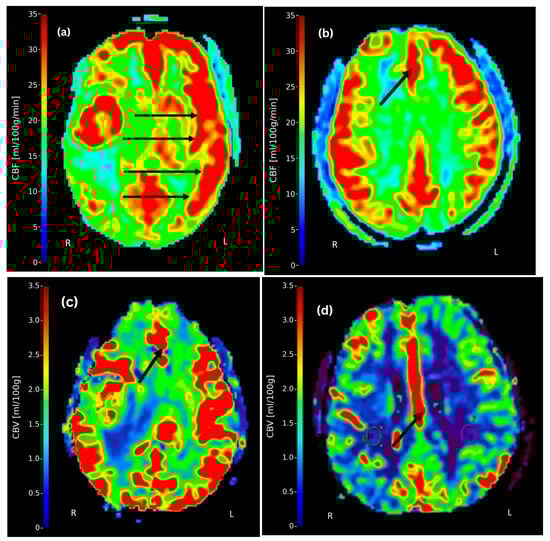

Assessment of Variability in Cerebral Blood Flow and Cerebral Blood Volume in Cerebral Arteries of Ischemic Stroke Patients Using Dynamic Contrast-Enhanced MRI

by Bilal Bashir, Babar Ali, Saeed Alqahtani and Benjamin Klugah-Brown

Tomography 2025, 11(11), 117; https://doi.org/10.3390/tomography11110117 - 22 Oct 2025

Background/Objectives: Cerebral blood flow (CBF) and cerebral blood volume (CBV) are critical perfusion metrics in diagnosing ischemic stroke. Dynamic contrast-enhanced magnetic resonance imaging (DCE-MRI) enables the evaluation of these cerebral perfusion metrics; however, accurately assessing them remains challenging. This study aimed to: (1) [...] Read more.

Background/Objectives: Cerebral blood flow (CBF) and cerebral blood volume (CBV) are critical perfusion metrics in diagnosing ischemic stroke. Dynamic contrast-enhanced magnetic resonance imaging (DCE-MRI) enables the evaluation of these cerebral perfusion metrics; however, accurately assessing them remains challenging. This study aimed to: (1) assess CBF asymmetry by quantifying and comparing it between contralateral hemispheres (right vs. left) within the MCA, ACA, and PCA territories using paired t-tests, and describe pattern of CBV; (2) evaluate overall inter-territorial regional variations in CBF across the different cerebral arterial territories (MCA, ACA, PCA), irrespective of the hemisphere, using ANOVA; (3) determine the correlation between CBF and CBV using both Pearson’s and Spearman’s correlation analyses; and (4) assess the influence of age and gender on CBF using multiple regression analysis. Methods: A cross-sectional study of 55 ischemic stroke patients was conducted. DCE-MRI was used to measure CBF and CBV. Paired t-tests compared contralateral hemispheric CBF in MCA, PCA, and ACA, one-way ANOVA assessed overall inter-territorial CBF variations, correlation analyses (Pearson/Spearman) evaluated the CBF-CBV relationship, and linear regression modeled demographic effects. Results: Significant contralateral asymmetries in CBF were observed for each cerebral pair of cerebral arteries using a paired t-test, with descriptive asymmetries noted in CBV. Separately, ANOVA revealed significant overall variability in CBF between the different cerebral arteries, irrespective of hemisphere. A strong positive correlation was found between CBF and CBV (Pearson r = 0.976; Spearman r = 0.928), with multiple regression analysis identifying age and gender as significant predictors of CBF. Conclusions: This study highlights hemispheric asymmetry and inter-territorial variation, the impact of age, and gender on CBF. DCE-MRI provides perfusion metrics that can guide individualized stroke treatment, offering valuable insights for therapeutic planning, particularly in resource-limited settings. Full article

Show Figures

Figure 1